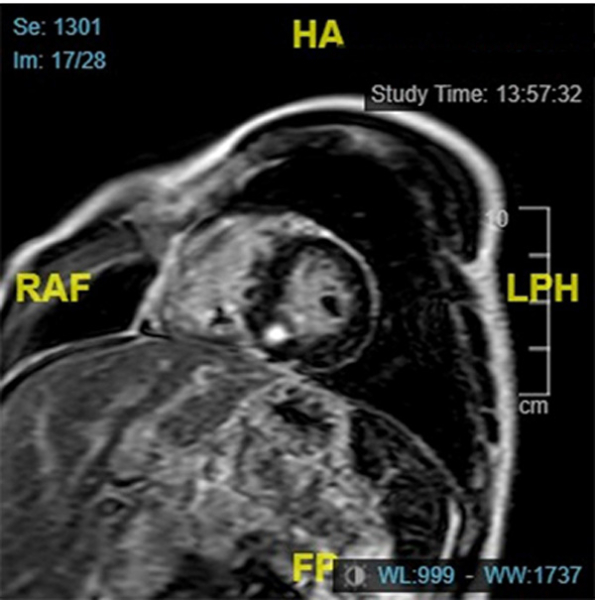

IRM

Figure 5

Figure 6

Figure 7

Figure 8 : Cartographie T1 N = 1000ms sur l’IRM 1,5 T

Conclusions de l’IRM :

- Cardiomyopathie hypertrophique asymétrique à prédominance septale (épaisseur maximale 19mm), sans atteinte VD

- Cinétique segmentaire homogène

- Zone de fibrose punctiforme inféro-septo-médiale isolée

- Absence d’allongement du T1